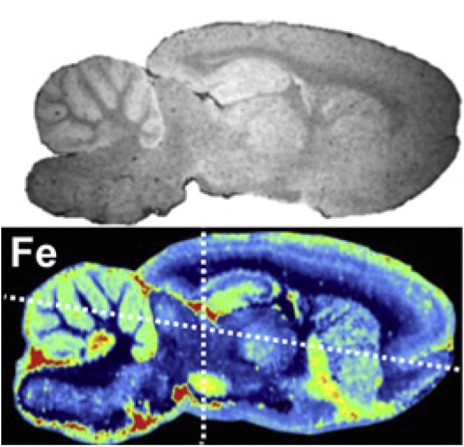

In 2005, Dr. Jozef Kaiser (Scientific Director of Atomtrace, Professor of Brno University, Head of Laser Spectroscopy Laboratory, Director of CEITEC Department of Physical Properties and Surface Science) published "Mapping of the metal intake in" in the European Physical Journal. Plants by large-field X-ray microradiography and preliminary feasibility studies in microtomography" (Eur. Phys. J. D 32, 113-118); in 2006, LIBS femtosecond laser spectroscopy was used to analyze plant samples of iron and manganese. The distribution of the elements and the first two-dimensional distribution of the complete leaf iron elements (see the image to the right), and published "Femtosecond laser spectrochemical analysis of plant samples" (Laser Phys.Lett.3, No.1, 21-25, 2006 )

The CEITEC/Atomtrace LIBS research team not only used LIBS technology to make complete leaf element distribution maps, but also used LIBS technology to combine with micro-CT (μCT) for 3D chemical imaging construction. The above research results have established the leading position of LIBS technology in the laser spectroscopy laboratory represented by Dr. Kaiser and others in the field of global life and environmental science applications.

The left picture shows the micro-CT of the root section of the sunflower, and the right picture shows the distribution of the lead metal in the sunflower root (from J. Kaiser et al., 2007).

The left picture shows the heavy metal pollution model, and the right picture shows the two-dimensional distribution of lead and magnesium concentrations in the leaves of corn, sunflower and lettuce LIBS.

In 2010, the laser spectroscopy laboratory represented by Kaiser used LIBS technology combined with μCT technology to study and analyze the distribution of spine bone elements including Ca, Al, P, Na, etc. of snake deformity osteitis, and published "Investigation of The osteitisdeformans phases in snake vertebrae by double-pulse laser-induced breakdown spectroscopy" (Anal. Bioanal. Chem. 398:1095-1107, 2010)

The picture above shows the snake spine μCT, the picture below shows the snake's normal vertebrae (a) and pathological vertebrae (b) two-dimensional distribution of calcium and phosphorus.